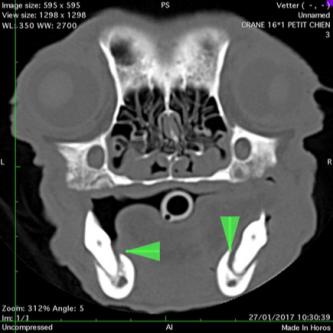

Otite moyenne: bulle tympanique opaque